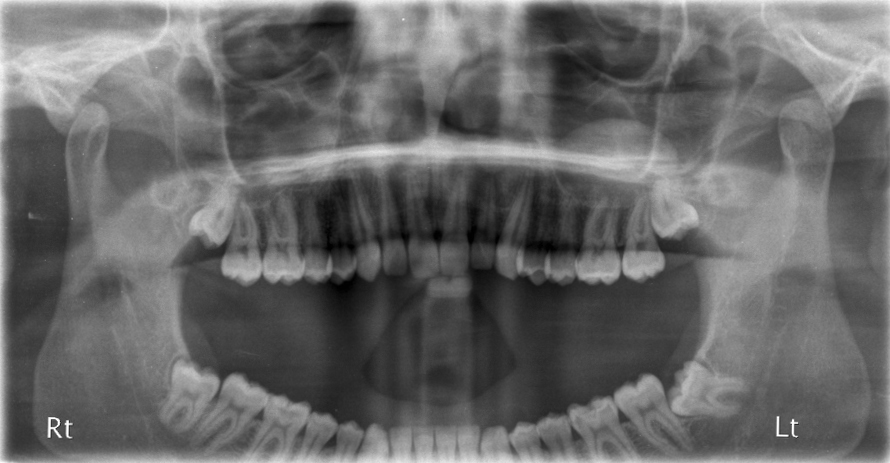

Mouth-Sinus Communications.

Mouth-Sinus Communications. Upper molar and premolar teeth often have their roots in close proximity to the sinus. In removing these teeth, there is a chance that a ‘hole’ can be made between the mouth & the sinus (this is sometimes not evident at the time of operation but may develop several weeks afterwards). If this ’hole’ persists or is left un-repaired, every time you drink, fluid can come out of the nose and you may develop a marked sinusitis. This ‘hole’ if small enough, can spontaneously close. It can be assisted in this by ‘cover plates’ that prevents food & fluids going into the sinus allowing the hole to close naturally. However, ‘holes’ above a certain size need to be surgically closed.